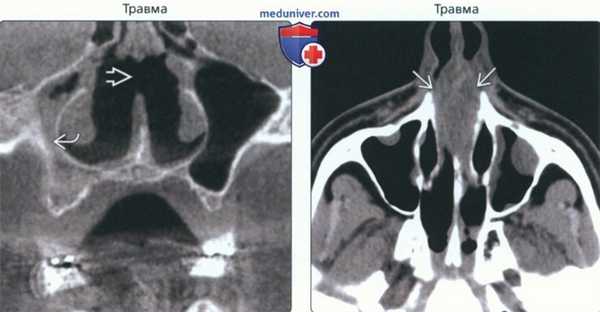

(Слева) На корональной КЛКТ определяется перфорация носовой перегородки после хирургического лечения по поводу хронического синусита. Определяются также признаки правостороннего гайморита.

(Справа) На аксиальной КТ без КУ в хрящевой и костной части носовой перегородки визуализируется экспансивный очаг, который клинически был расценен как гематома, хотя и не выглядит гиперденсным на КТ. Гематома обусловлена травмой этой области.

• Травма:

о Перелом перегородки → гематома → некроз вследствие ишемии или разрыв слизистой оболочки с обнажением хряща